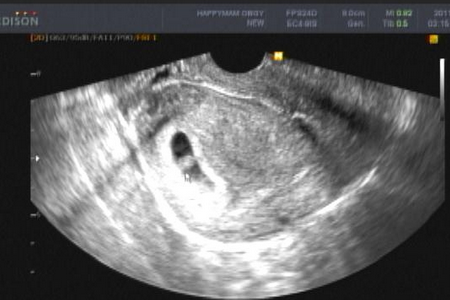

怀孕两个月胎儿发育情况

孕2月胎儿迅速生长,与孕早期心脏和大脑的发育时的速度相当,并在几周中显现出明显的轮廓。到第8周末,胎儿将长到3厘米左右、体重约有4克;胎盘脐带形成;皮肤像纸一样薄,血管清晰可见;用肉眼就能分辨出头、身体和手足;已经会做踢腿、伸腿、抬手、移动双臂的小动作了——不过此时丝毫也查觉不到。